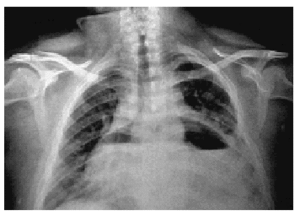

En los días posteriores, fue produciéndose una progresiva acumulación de líquido en el saco pericárdico, de tal forma que observamos un llamativo nivel hidroaéreo en la cavidad pericárdica (fig. 2). El hidroneumopericardio es un hallazgo radiológico poco frecuente, sobre todo cuando es de tipo iatrogénico tras punción pericárdica. Finalmente, ante dicha evolución y la aparición de signos clínicos de taponamiento cardíaco, se efectuó ventana pleuropericárdica, cuyo curso posterior fue satisfactorio.

Figura 2.